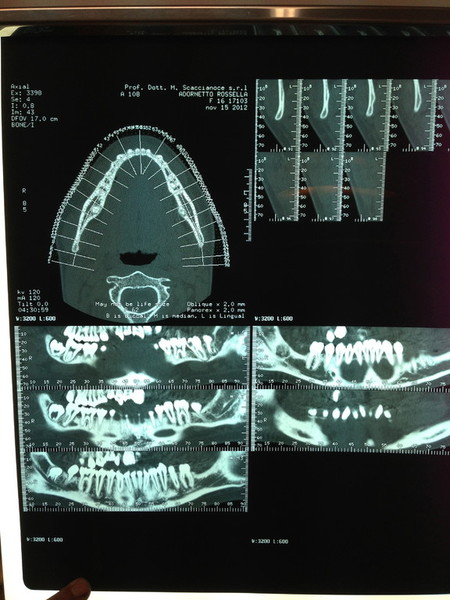

Paziente candidato a intervento di chirurgia Ortognatica